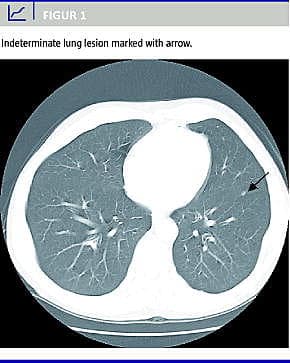

Hos otte af disse 22 patienter (36%) progredierede infiltraterne (Figur 1 ) i størrelse og/eller antal. En af patienter viste sig at have en primær lungecancer og en anden et malignt lymfom. Hos de resterende seks patienter (27%) fandtes manifeste lungemetastaser mediant 15 måneder efter den primære operation. Dette var signifikant forskelligt fra patienterne med normale fund ved CT af thorax præoperativt, hvor kun 6% udviklede maligne forandringer i lungerne i opfølgningsperioden (p < 0,0001). Udviklingen af lungemetastaser var signifikant relateret til lymfeknudemetastaser i operationspræparatet og postoperativ forhøjelse af karcinoembryonalt antigen (CEA).